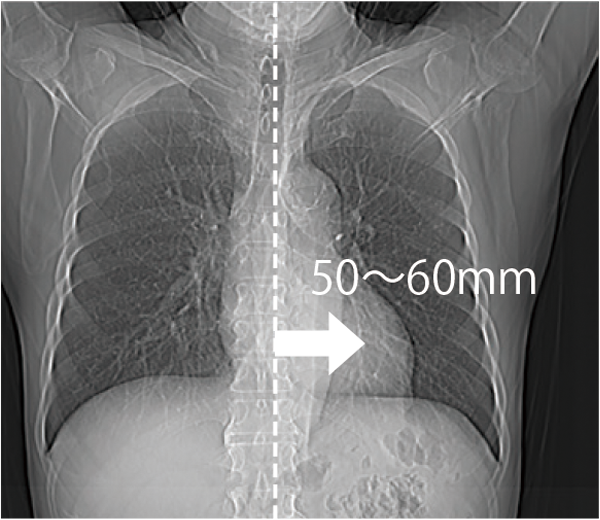

The patient table can move horizontally up to 200 mm, making it easier to position the scanned region in the center, even in cardiac or orthopedic areas, such as the shoulder. This is expected to improve examination efficiency.

Positioning the heart near the center of the field of view